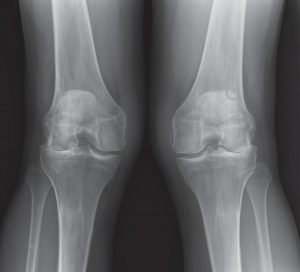

PARTIAL KNEE REPLACEMENT:LATERAL COMPARTMENT

MAKO ROBOTIC-ARM ASSISTED

Dr. Buechel is a highly experienced Lateral Partial Knee Replacement Specialist and uses the Mako Robot Partial Knee System to ensure a personalized precision implant installation for every lateral patient. Dr. Buechel has performed several hundred Robotic lateral partial knees and performs them routinely, and results are life-changing.